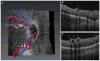

Methods: Bedside noncontact SD-OCT imaging was performed after obtaining parental consent on 97 consecutive infants between January 2009 and September 2012. Fifty-seven subjects (31-49 weeks' post-menstrual age) who had an SD-OCT scan in at least 1 eye showing the edge of the optic nerve and at least 1 major retinal vascular arcade were included. One eye per subject was randomly selected for analysis. Two masked graders evaluated scans for (1) retinal vessel elevation, (2) scalloped retinal layers, (3) hyporeflective vessels, and (4) retinal spaces. To coalesce the weight of these features, a Vascular Abnormality Score by OCT (VASO) was created. For quantitative assessment of vessel elevation, retinal surface maps were created.

Results: From among 67 SD-OCT characteristics that were recorded, the most common characteristics found were vessel elevation (44%), hyporeflective vessels (40%), scalloped layers (22%), and retinal spaces (11%). Features significantly associated with plus disease were vessel elevation (P = 0.01), hyporeflective vessels (P = 0.04), and scalloped retinal layers (P = 0.006). Intragrader agreement was between 74% and 90% for all features. The VASO was significantly higher in subjects with plus disease (P = 0.0013). On 3-dimensional SD-OCT volumes, eyes with plus disease had greater retinal surface elevation that more often matched en face retinal vascular patterns.

Conclusions: We present a novel 3-dimensional analysis of vascular and perivascular abnormalities identified in SD-OCT images of eyes with ROP. The SD-OCT characteristics that are more common in eyes with plus disease provide the first in vivo demonstration of the effects of vascular dilation and tortuosity on perivascular tissue. The VASO and surface maps also delineate the severity of vascular pathology in plus disease. Further studies evaluating these findings in eyes with pre-plus versus normal posterior pole vessels may determine the usefulness of SD-OCT in the early detection of vascular abnormalities in ROP.